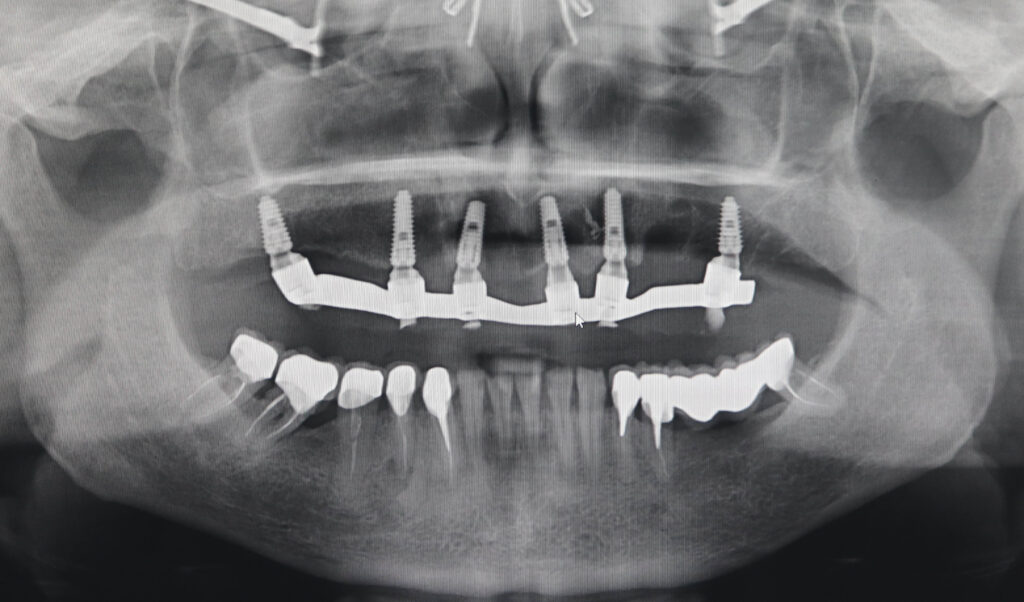

снимок

Было произведено удаление зубов на верхней челюсти и проведена комплексная имплантация по системе All-on-6.

Установлены 6 имплантатов Megagen AnyRidge.